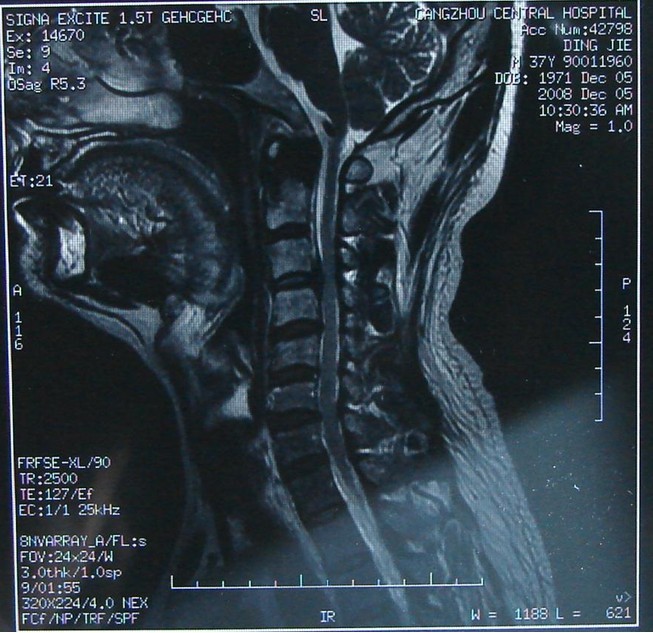

mri显示颈椎有狭窄

图片尺寸900x1200